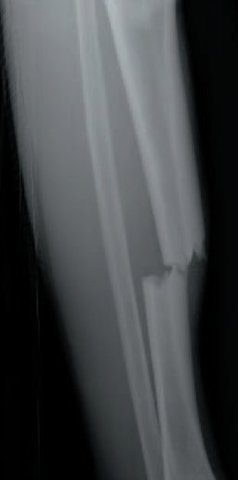

• Broke my leg

Broke my leg

i was playing hockey and a kid stuck his leg out and broke my leg in two places